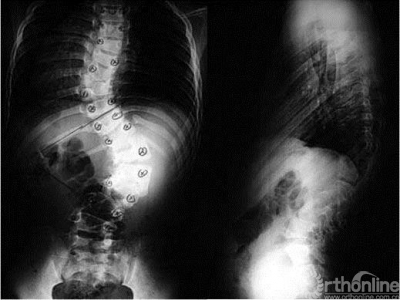

14岁男性患儿,先天性脊柱侧凸,术前、术后及外观对比